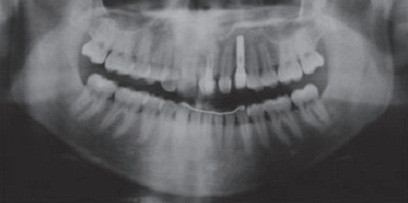

女,十岁,单侧唇腭裂致21牙、22、12牙畸形,且21牙、22牙间牙槽骨发育不全。经自体髂嵴骨移植后,拔除21牙、22牙行正畸治疗以将23牙移动至22牙位置。同时将正畸需拔除的下颌第一前磨牙移植到21牙的牙槽窝内。并在正畸治疗结束后树脂恢复21牙、22牙形态。患者18岁时拔除左上颌乳尖牙行种植义齿修复。